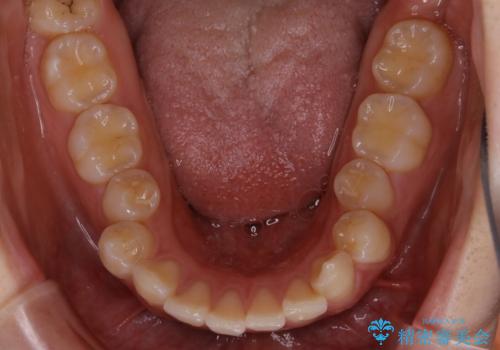

- 前歯の重なりが気になるとご相談にいらした方です。前歯のがたつきは奥歯の噛み合わせのズレが原因となっていたため、インビザラインFULLにて奥歯からしっかり治療していきました。

前歯のがたつきだけを治そうとした場合、噛み合わせは二の次なってしまう事が多く、せっかく綺麗になった歯並びも後戻りしやすくなります。

見た目だけでなく奥歯を移動させて噛み合わせの改善までが行えるのはインビザラインであるからこそです。奥歯の噛み合わせからしっかり機能させることで、長期間にわたって綺麗な歯並びを保ちやすくなります。